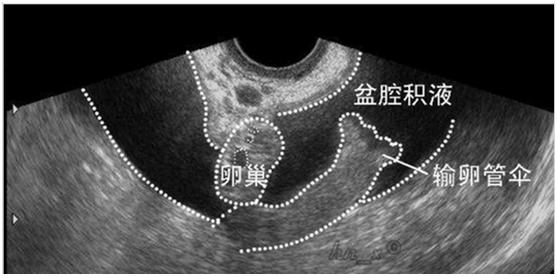

受精卵在子宫体腔以外着床的现象称为异位妊娠,最常见的是输卵管妊娠。当输卵管妊娠流产或破裂,就会输卵管壁破裂出血,血液聚积在子宫直肠陷凹,进而形成盆腔积液。从后穹窿可以抽吸出不凝固血液。